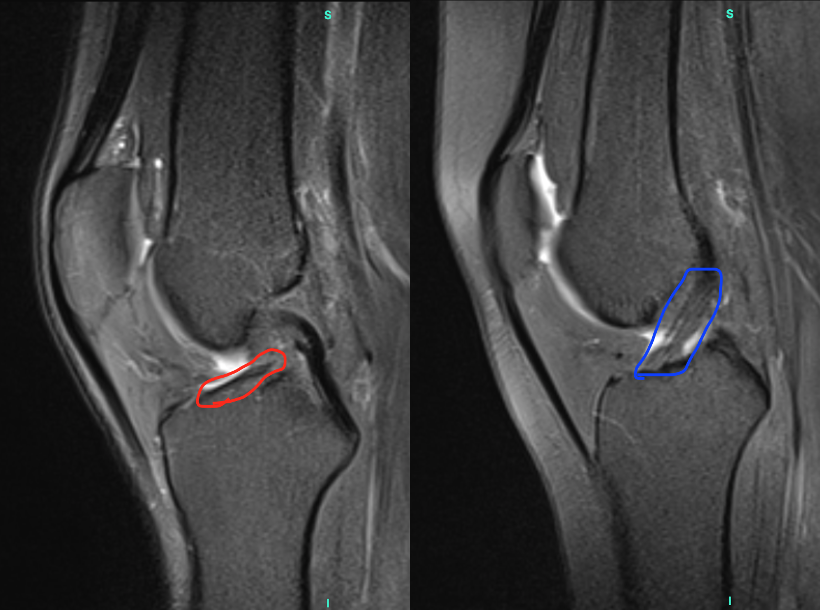

Comparativo de Ressonância Magnética (RM) do joelho em plano sagital. (A) LCA com ruptura completa, destacado em vermelho, demonstra descontinuidade das fibras. (B) LCA íntegro, destacado em azul, exibe fibras contínuas.

Figura 2. Comparativo de Ressonância Magnética (RM) do joelho em plano sagital. (A) LCA com ruptura completa, destacado em vermelho, demonstra descontinuidade das fibras. (B) LCA íntegro, destacado em azul, exibe fibras contínuas.